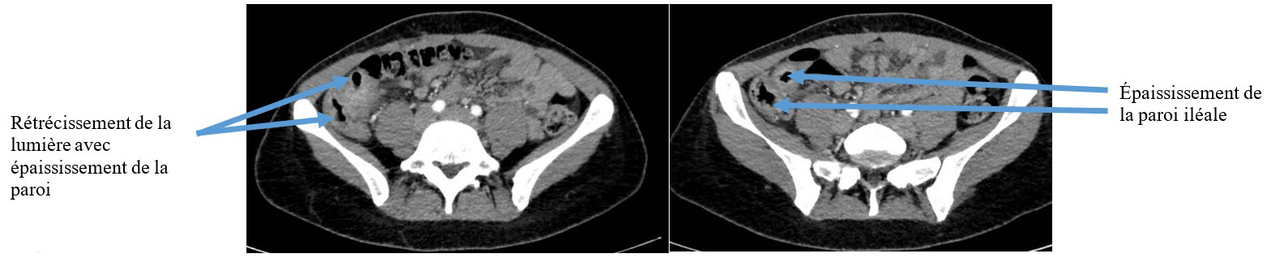

– une colite aiguë grave pouvant être inaugurale d’une maladie inflammatoire chronique de l’intestin (MICI). Ici, c’est un diagnostic possible car la patiente décrit des troubles digestifs évoluant depuis plusieurs années et elle fume, ce qui est un facteur de risque de développer une maladie de Crohn. Les critères de Truelove et Witts définissent la colite aiguë grave : > 6 selles sanglantes/24 h + protéine C réactive (CRP) > 30 mg/L ou hémoglobine < 10,5 g/dL ou température > 37,8 °C OU fréquence cardiaque > 90 bpm.